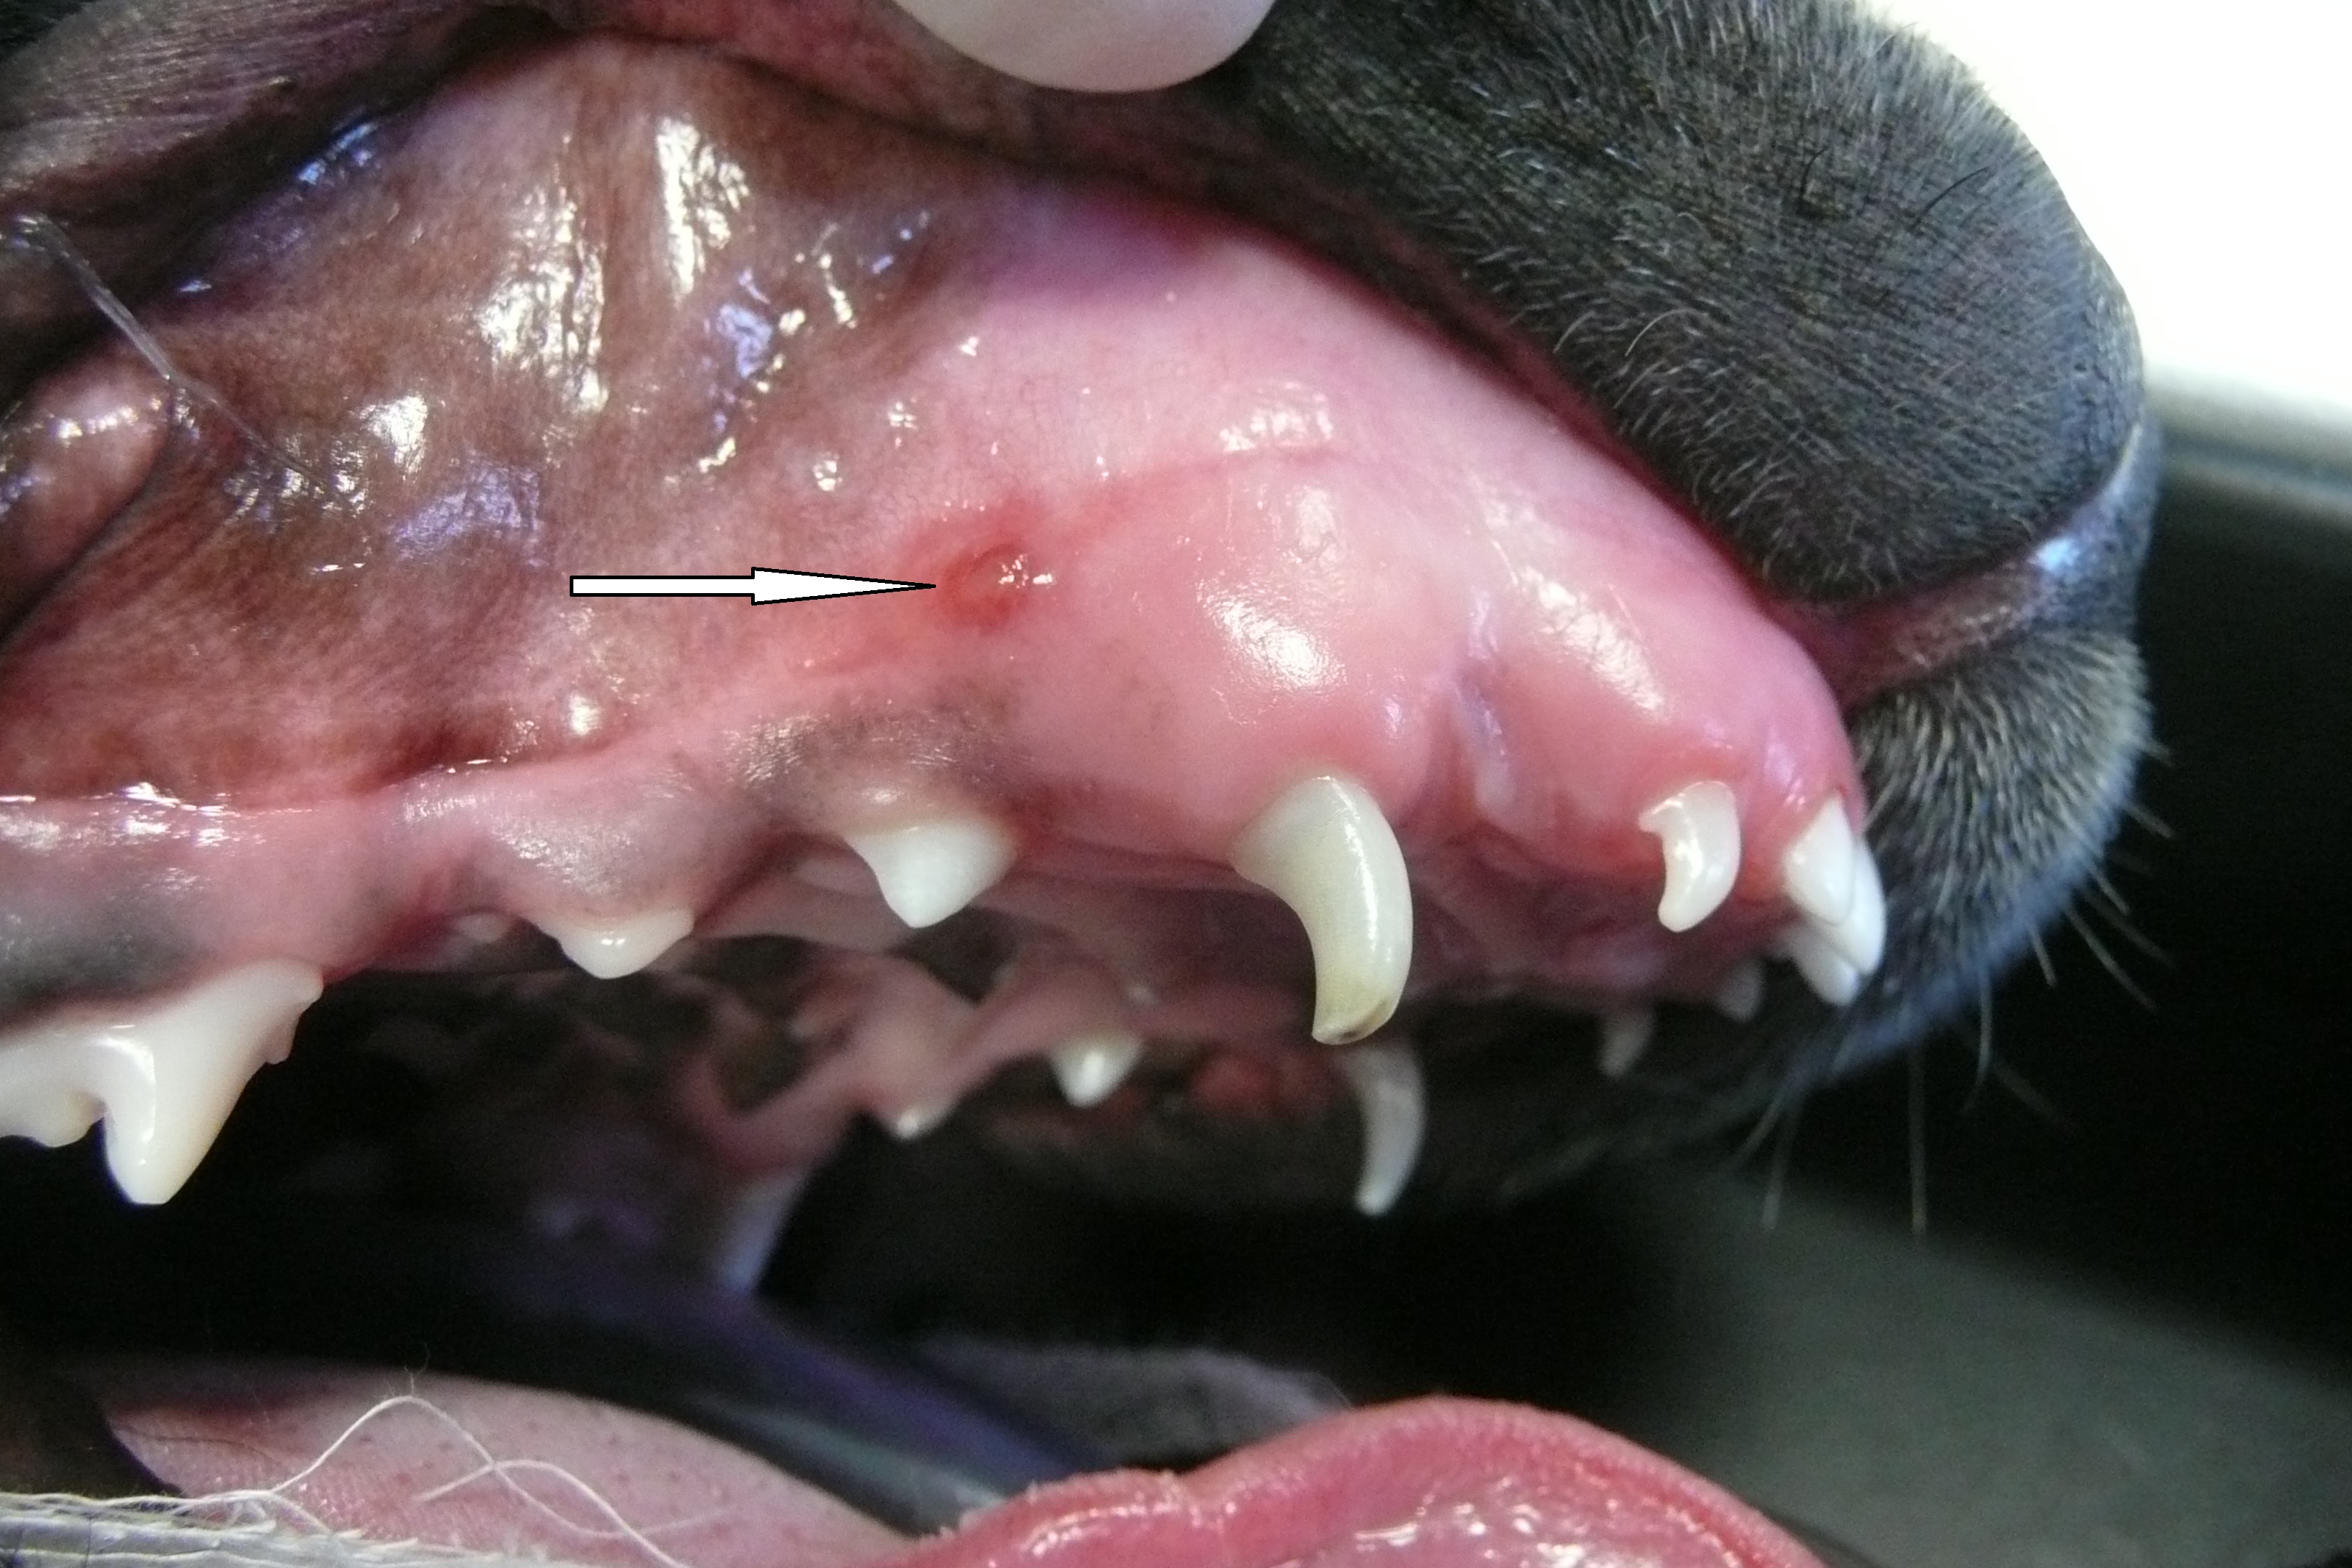

Fractures usually occur following blunt trauma to the teeth. Sometimes this will just be damage to the enamel and dentine, but sometimes this can result in damage to the pulp as well. Exposure of the pulp and the nerves within it is extremely painful at the time of injury, and an exposed pulp provides an open channel for bacteria to penetrate into the bone of the jaw. An exposed pulp with either bleed or show as a pink ring initially, and as the pulp decays will show as a black circle.

Fracture of the right madibular canine. In this case, the open pulp chamber is clearly visible and the fracture extends below the level of the gum

Above: Complicated Crown Fracture of right mandibular canine with exposed necrotic pulp (black circle at fracture site.